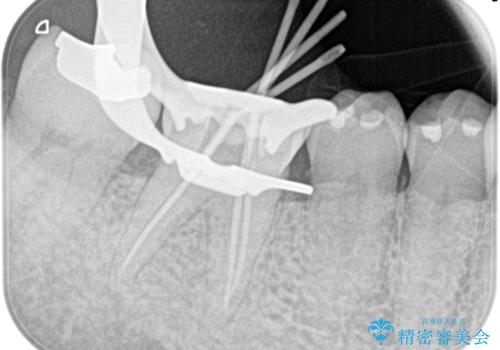

- 1週間前から冷たいもので強い持続痛を感じることを主訴に来院されました。

歯髄診断と痛みの再現により原因歯を特定し、症候性不可逆性歯髄炎の診断となりました。

根管治療〜オールセラミッククラウン(エクセレント)の治療を行なっております。